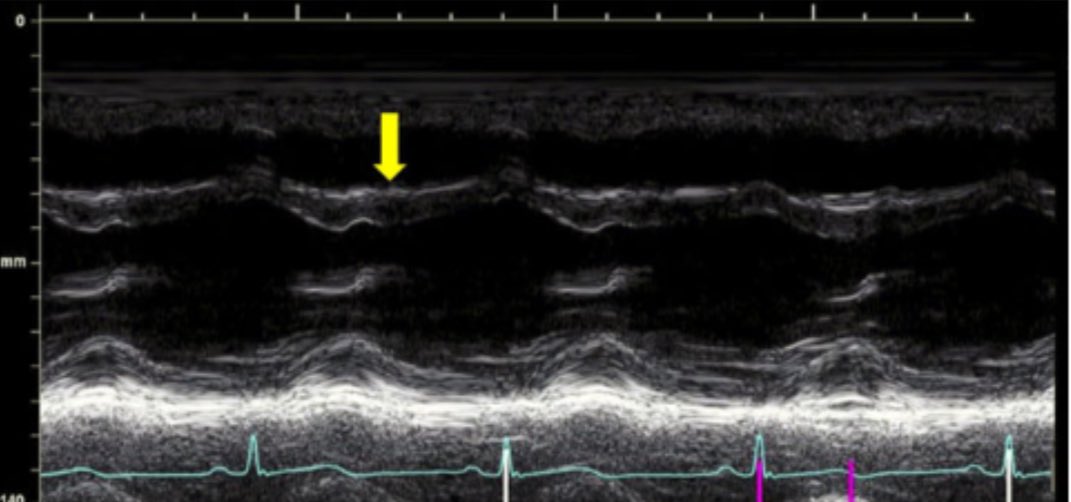

π Right Ventricular Pressure Overload

β Septal flattening during systole (yellow)

β Worsened during inspiration (red)